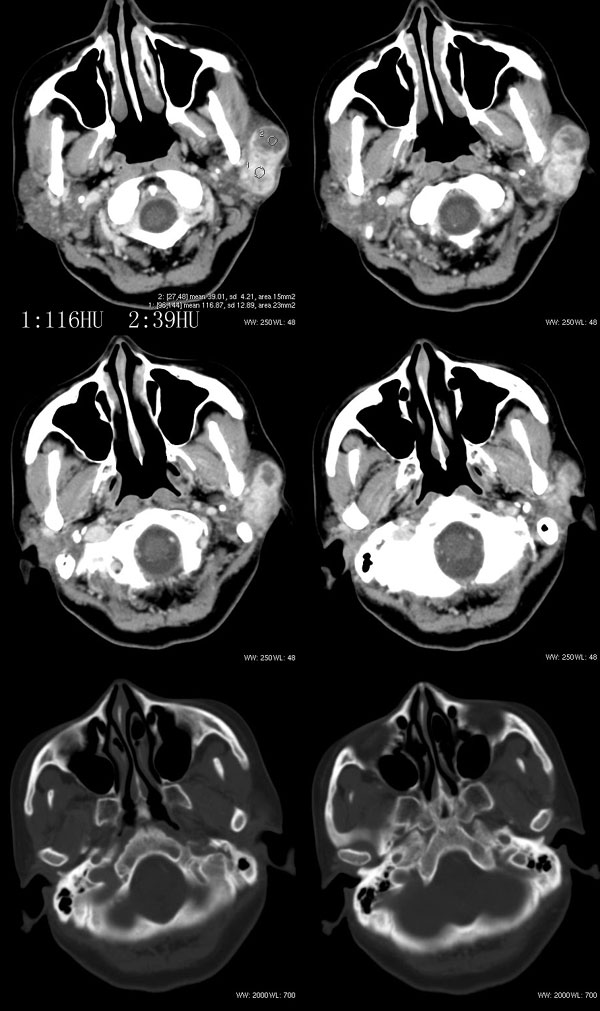

女性,43岁。左腮部肿物5年。体检:(肿物)质中,约5x4x4cm,边界清,固定。

左腮腺肿物,内可见低密度坏死区,增强扫描示肿块明显强化,且呈持续延迟强化,常规考虑腮混合瘤可能性大,但强化表现不太符合,不除外腮腺纤维血管瘤、神经鞘瘤、淋巴瘤及巨淋巴结增生症

左侧腮腺多形性腺瘤可能性大。1、是混合瘤中最常见的良性肿瘤;2、中年女性多见并且时间长症状轻;3、病灶内有低密度坏死区,增强时强化;4、其内有钙化,囊性部分未强化;5、需与囊性淋巴瘤相鉴别。